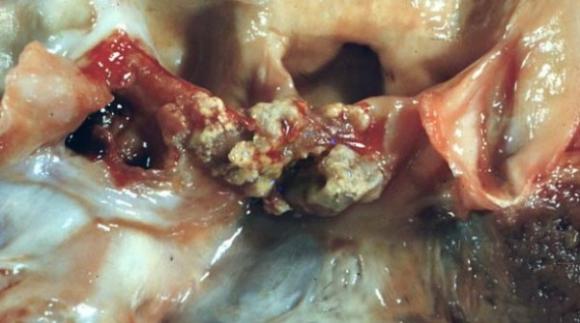

Científicos Argentinos de la UBA desarrollan un método para identificar las causas de una infección del corazón